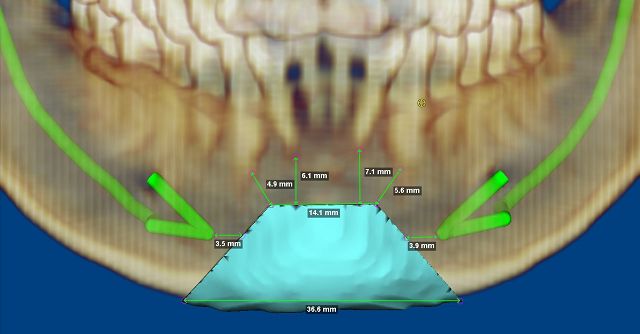

為避免術中神經損傷,季照芸主任先利用3D立體列印頦舌肌下頷成型手術,事先以3D電腦斷層立體模擬,客製化患者的神經齒根位置,同時預期術後外觀,除改善呼吸道空間,更能處理下巴後縮與歪斜等問題;另配合處理上呼吸道結構異常,同步進行懸壅垂顎咽成型手術、咽喉側壁成型手術及舌根減積手術。術後王先生每小時窒息指數從65.5次降至13.5次,且同時改善下巴後縮和歪斜,不僅解決上呼吸道狹窄問題,也讓歪斜的外表得到美化。